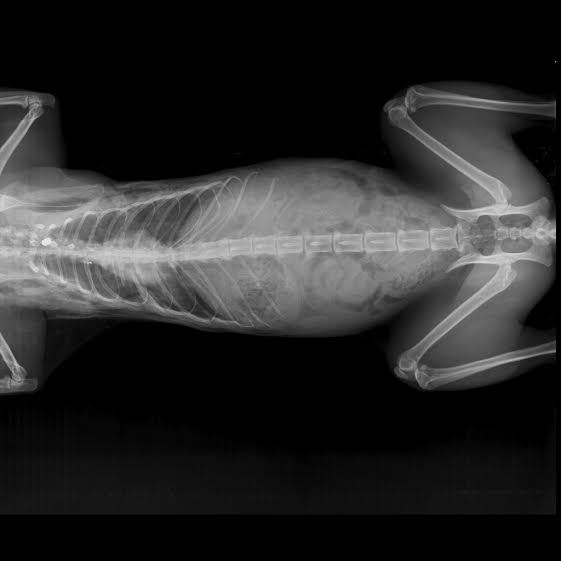

2) Γουόκερ: Βρέθηκε πυροβολημένος στην σπονδυλική στήλη στην οδό Ανδριτσαίνης στο Γαλάτσι τον Ιανουάριο του 2015 με δύο μέρες διαφορά από τον Λόττο. Το γατί πυροβολήθηκε δίπλα σε παιδική χαρά και στο 6ο Γυμνάσιο. Παραμένει παράλυτο.

GalatsiPyrovolimenosParalytosGouoker2015 (1) Το σφαιρίδιο στην σπονδυλική στήλη του Γουόκερ.